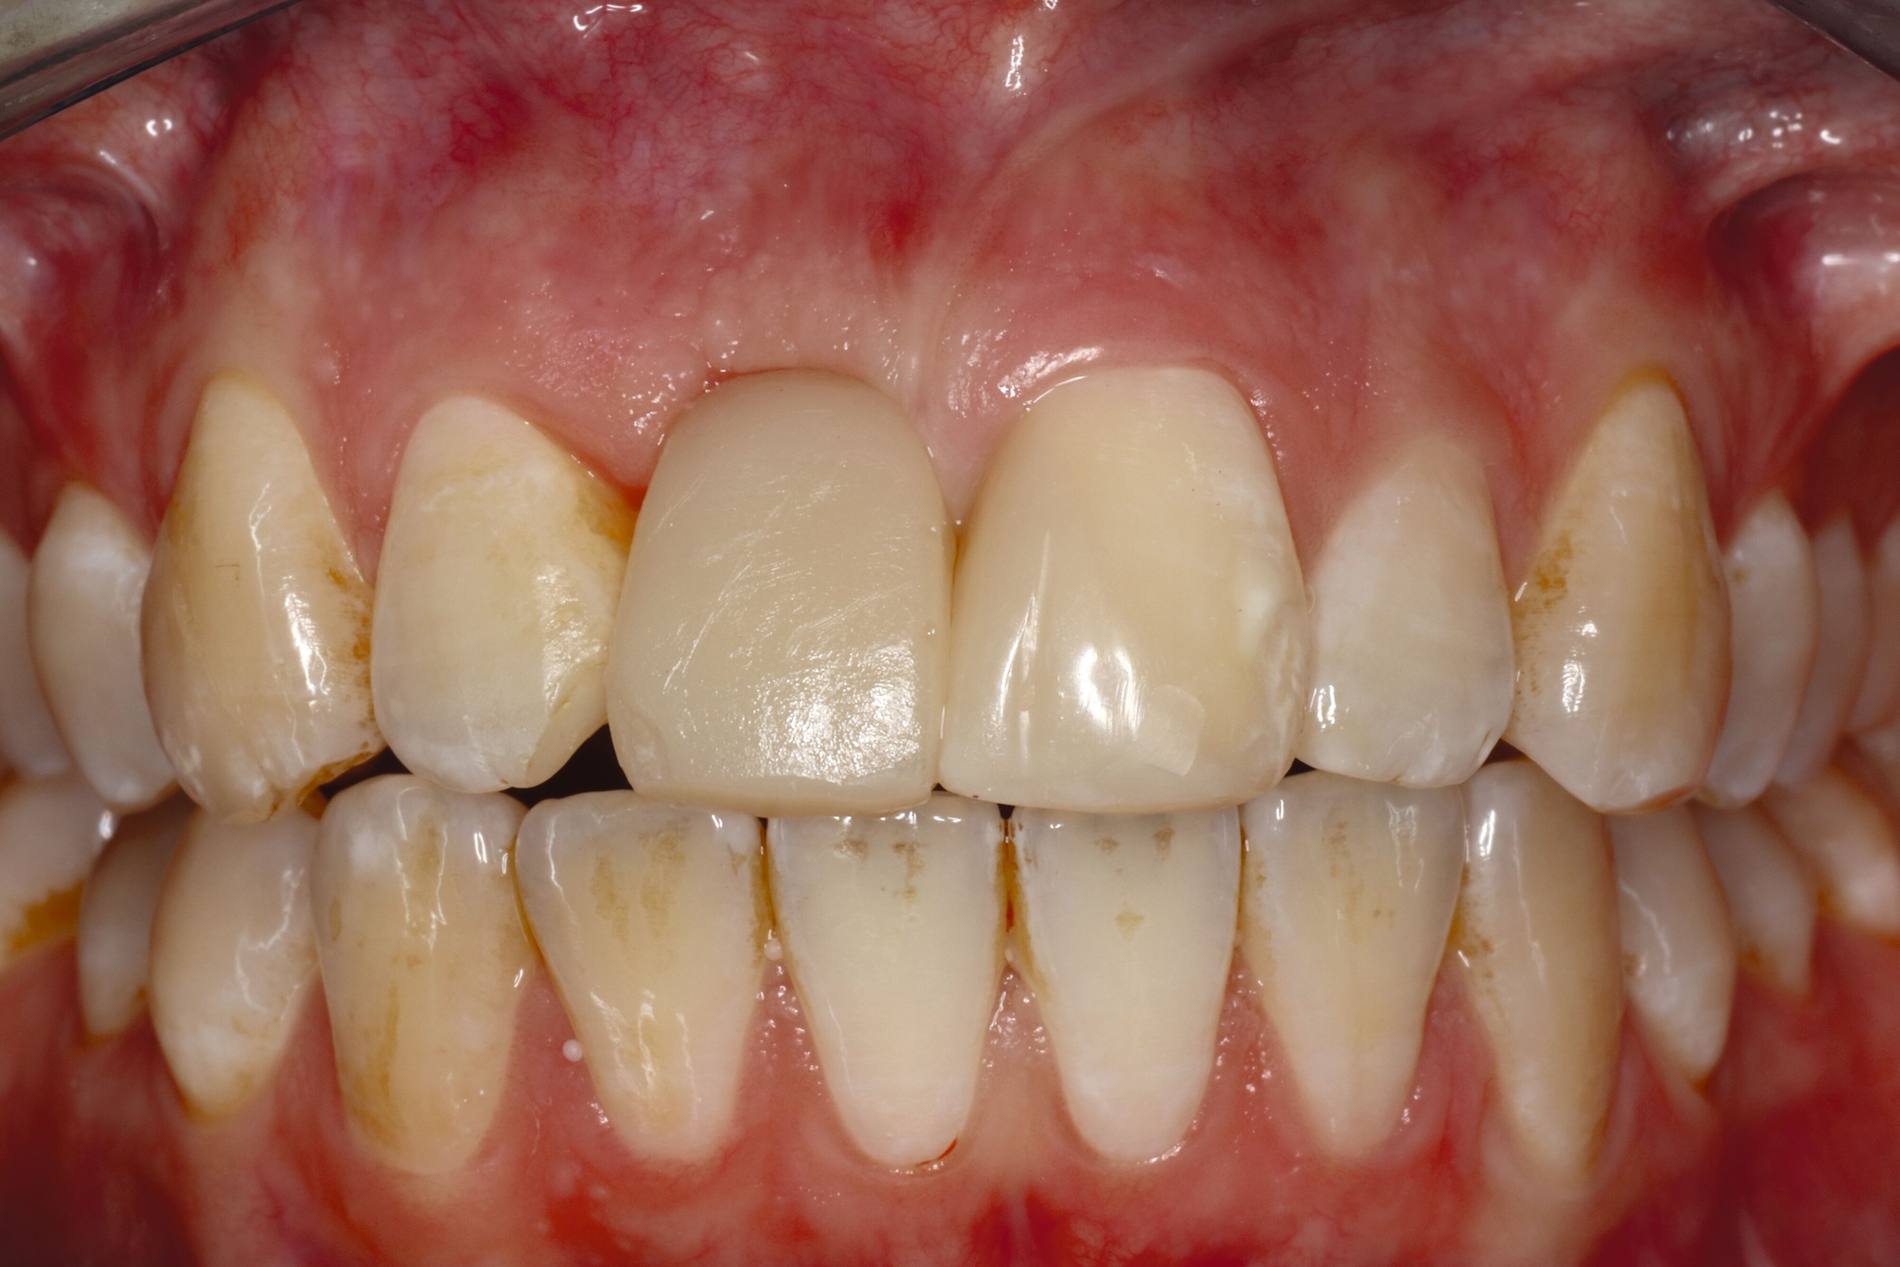

Restaurative Versorgung nach Zahntransplantation oder nach kieferorthopädischem Lückenschluss

Wenn die Lückenversorgung durch eine Transplantation (siehe Teil 4 der Fortbildung „Dentales Trauma“: Chirurgische Aspekte) oder einen kieferorthopädischen Lückenschluss (siehe Teil 5 der Fortbildung „Dentales Trauma“: Kieferorthopädische Aspekte) vorbereitet wurde, beschränkt sich die restaurative Versorgung auf eine Formkorrektur der Zähne. Diese kann – je nach Situation und Präferenz des Behandlers – mit direkten (Abbildung 4) oder mit (minimalinvasiven) indirekten Restaurationen (Veneers, Teilkronen) erfolgen. Gerade bei jungen Patienten muss allerdings berücksichtigt werden, dass im Zuge der passiven Eruption [Mele et al., 2018] Veränderungen des Gingivaverlaufs an den restaurierten Zähnen zur Exposition der Restaurationsränder führen und eine neue Versorgung nach mehreren Jahren erforderlich machen können.